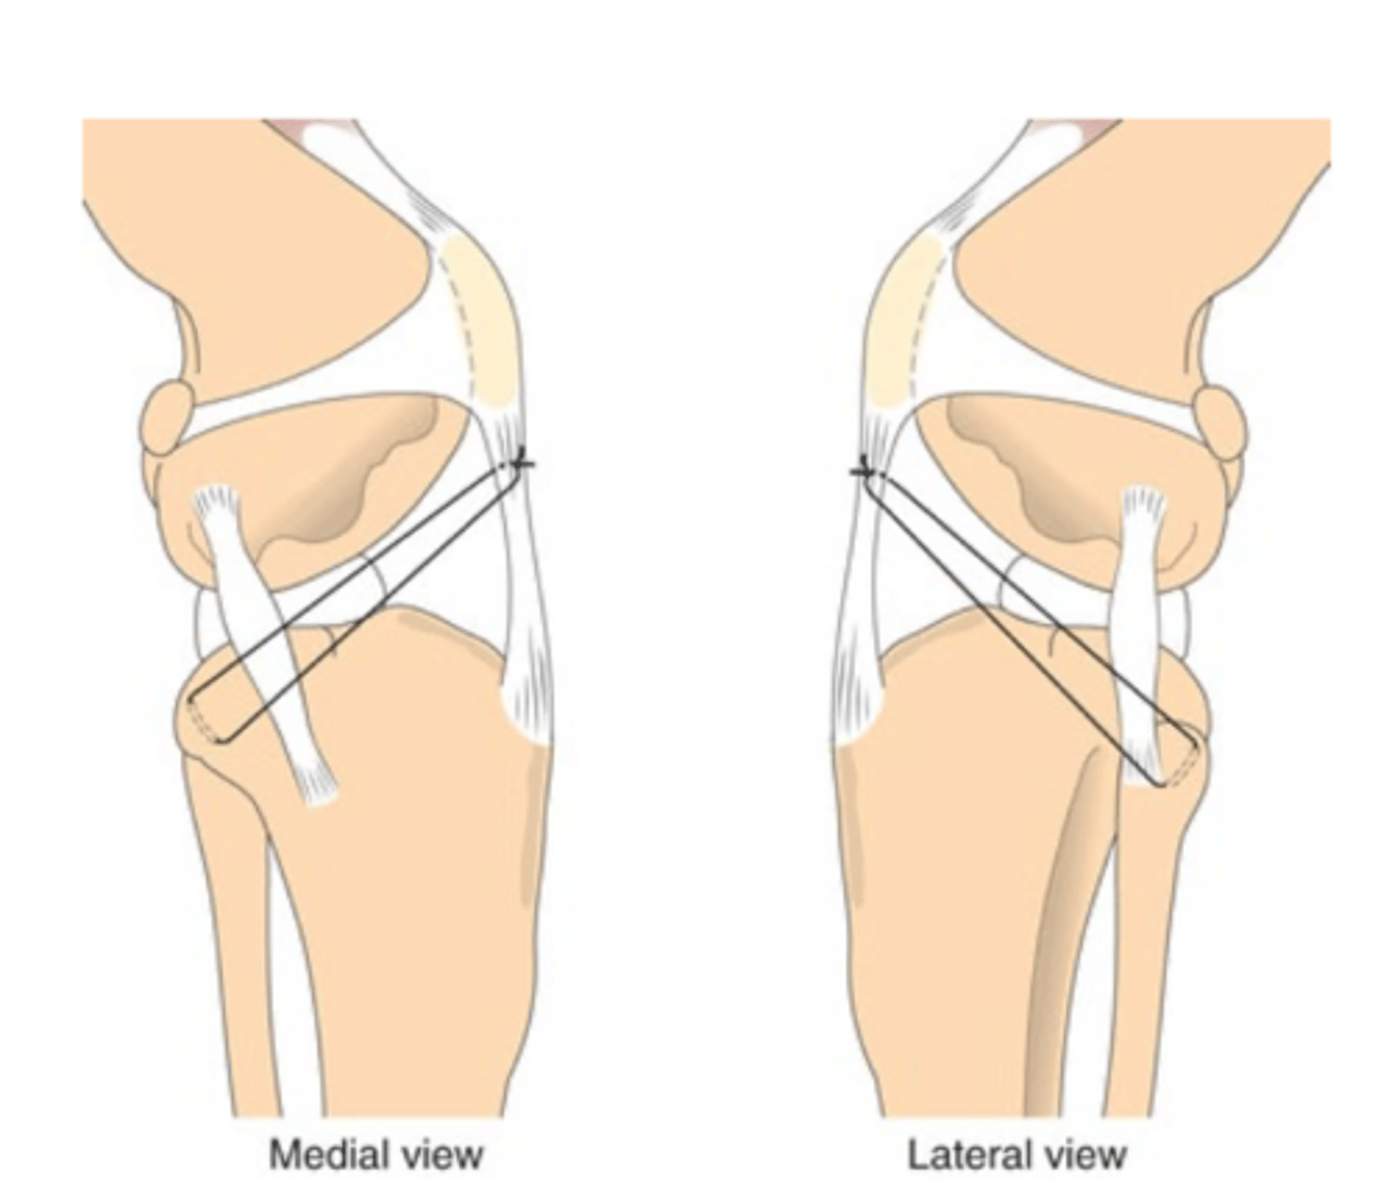

extracapsular imbrication...done in opposite direction of CCLD placement

what technique is used to sx. repair CaCL rupture